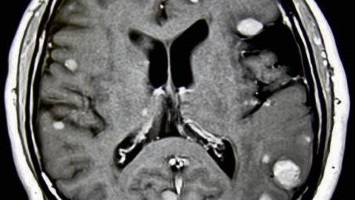

Aminosäuren-PET bei Hirnmetastasen

Ein spezielles bildgebendes Verfahren, die Aminosäuren-PET, kann nicht nur die Patientenversorgung verbessern, sondern auch die Forschung zur Entwicklung neuer Therapieansätze vorantreiben.